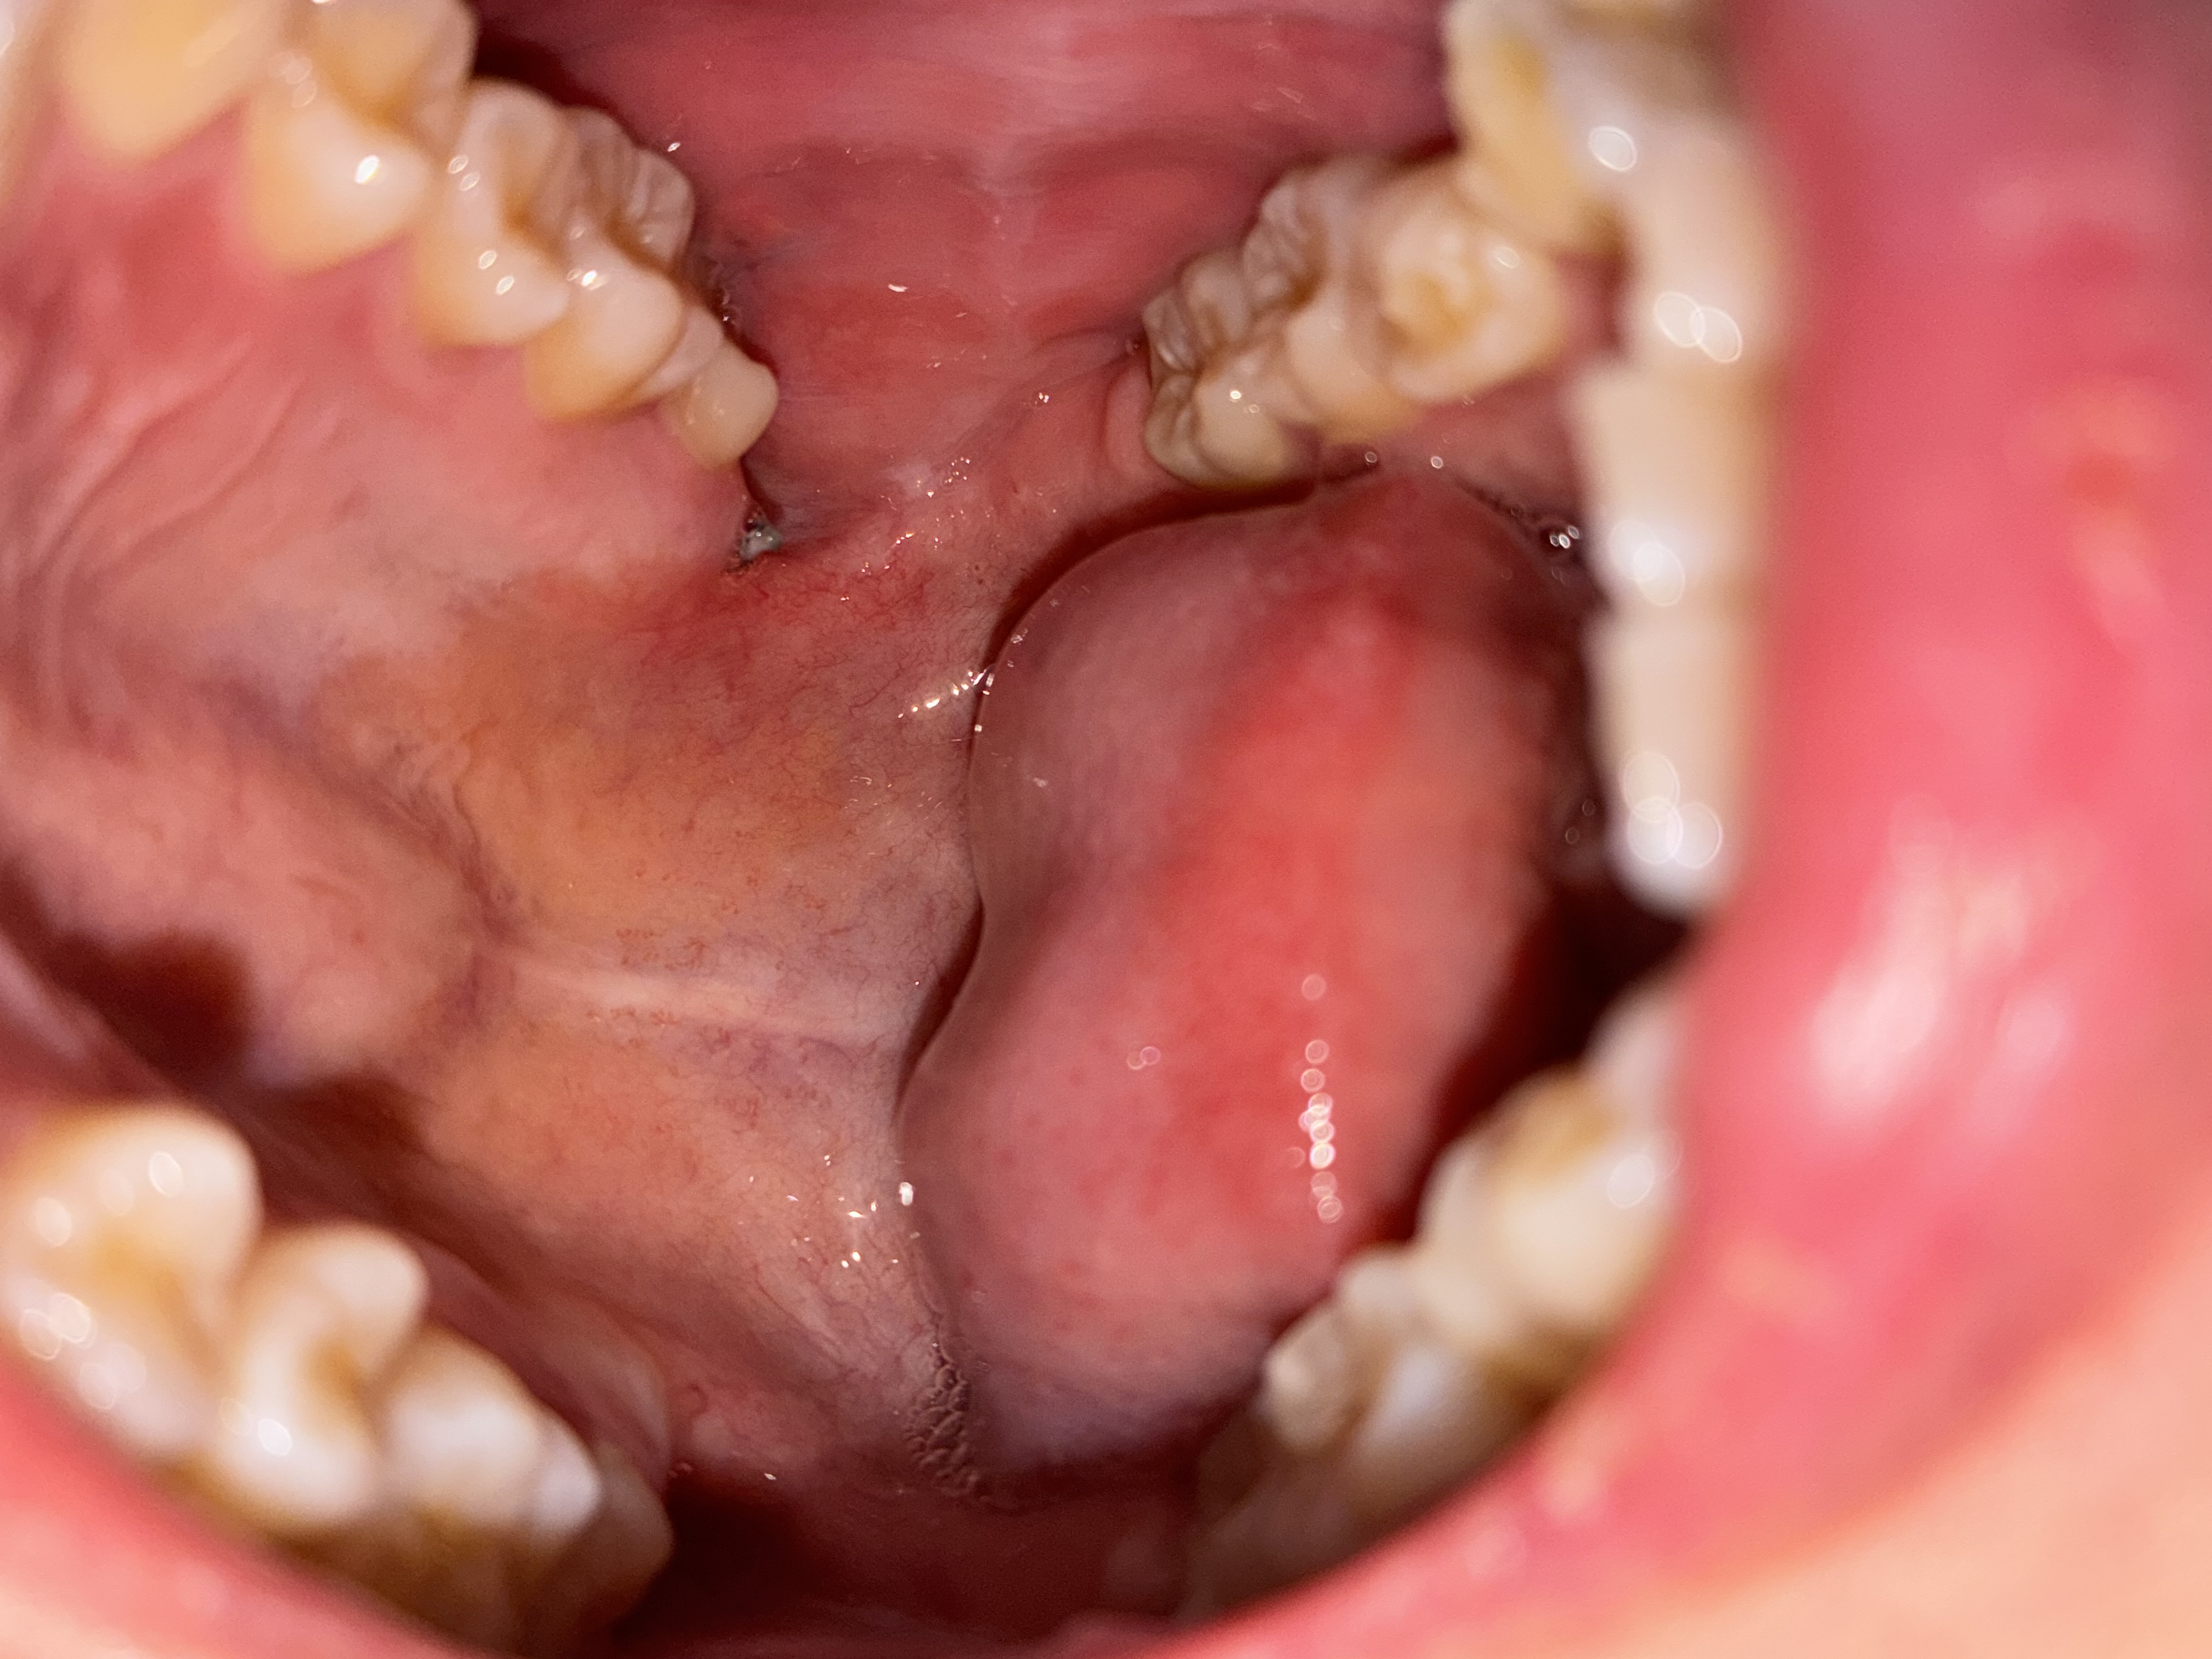

親知らず抜歯後、縫合部よりも奥の部分が痛みます。